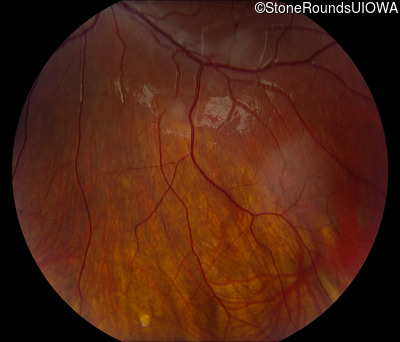

Fundus Photography - Right - 20/30

Exemplar